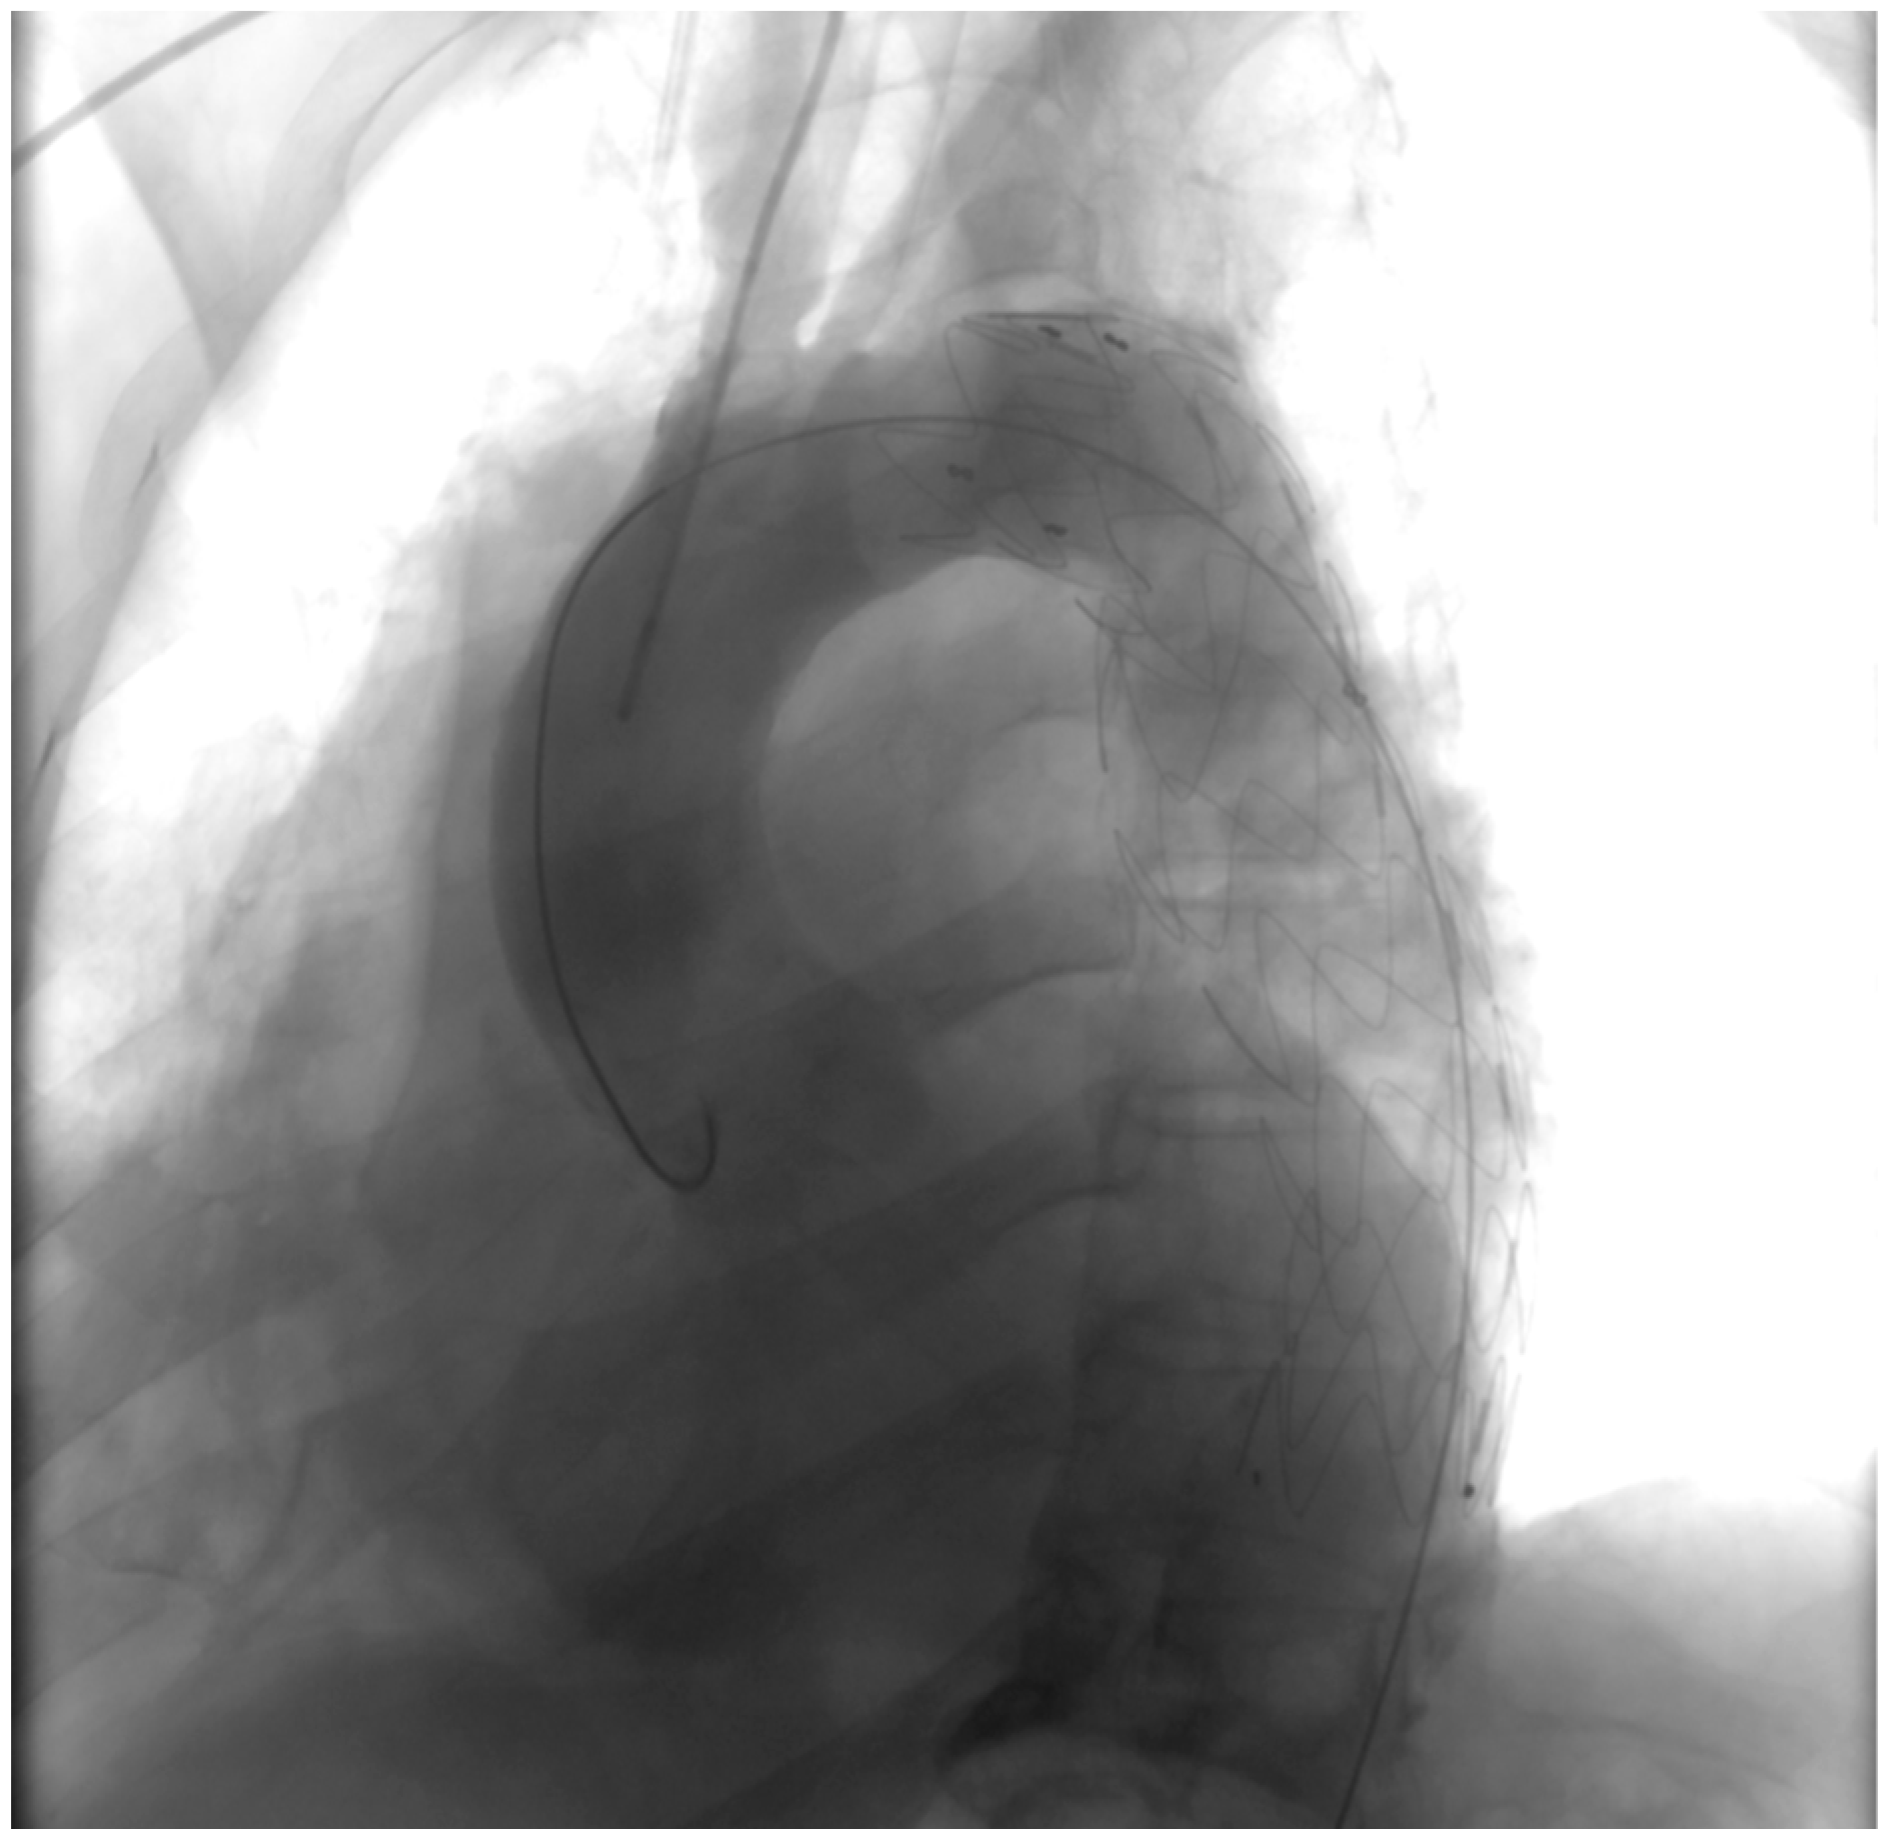

Post-intervention assessment (Figure 5).

Figure 5.

Post-intervention assessment.

Following the deployment of the covered stent graft, contrast injection revealed a sealed and reinforced aortic wall, effectively closing the breach created by the PAU. This visual documentation serves as a compelling affirmation of the success achieved through the endovascular intervention.